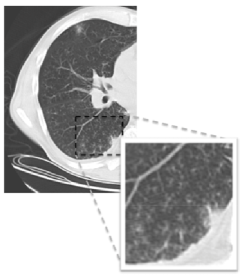

As shown by the recent pandemic of novel swine-origin H1N1 influenza, respiratory tract infections are a leading cause of disability and death. A common image pattern often associated with respiratory tract infections is TIB opacification, represented by thickened bronchial structures locally surrounded by clusters of 2-3 millimeter micro-nodules. Such patterns generally represent disease of the small airways such as infectious-inflammatory bronchiolitis as well as bronchiolar luminal impaction with mucus, pus, cells or fluid causing normally invisible peripheral airways to become visible [1]. Fig. 1 shows TIB patterns in a chest CT.

II. Learning characteristics of TIB patterns: From Fig. 1, we can readily observe that TIB patterns have intensity characteristics with high variation towards nearby pixels, and such regions do not usually exceed a few millimetre(mm) in length. In other words, TIB patterns do not constitute sufficiently large homogeneous regions. Non-smooth changes in local gradient values support this observation. As guided by these observations, we conclude that (a) TIB patterns are localized only in the vicinity of small homogeneous regions, and (b) their boundaries have high curvatures due to the nature of its complex shape.